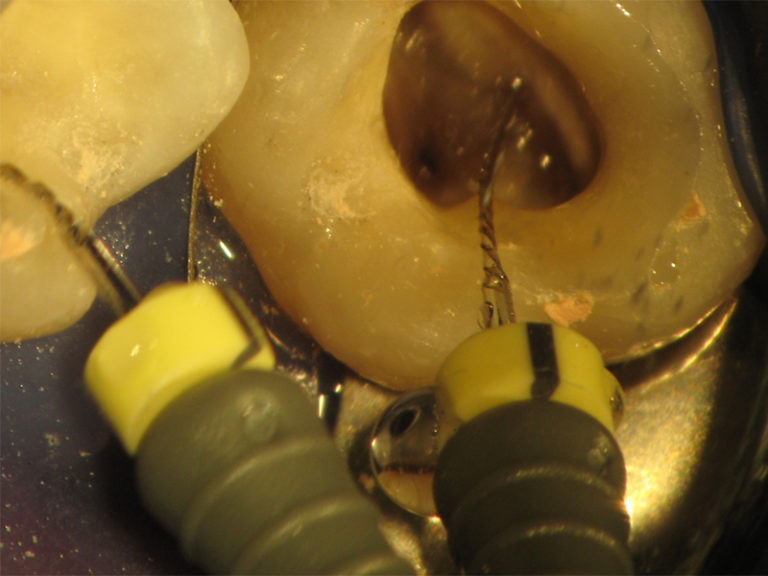

In den letzten Jahren kam es zu enormen Fortschritten in der Endodontie. Durch den Einsatz flexibeler Instrumente (Nickl-Titan- Instrumente), der elektronischen Längenmessung (Raypex) und Ultraschall aktivierter Spülungen sowie der Einführung von Dentalmikroskopen die das sehen und behandeln kleinster Zahnstrukturen ermöglichen, konnte in Wissenschaftlichen Studien eine Erfolgsquote von bis zu 95% ermittelt werden.

Anschließend wird das erkrankte Hartgewebe des Zahnes entfernt und durch eine Kunststoff- Aufbaufüllung ersetzt. Für den Zugang zu den feinen Kanalstrukturen wird eine kleine Öffnung in die Kaufläche des Zahns präpariert und die Wurzelkanaleingänge unter Einsatz des Dentalmikroskops dargestellt und erweitert. Es folgt die eletrometrische Zahnlängenbestimmung um sicherzustellen dass die Aufbereitung der Wurzelkanäle bis zum wirklichen Ende des Kanalsystems erfolgt. Bei diesem zurzeit genausten Verfahren der Zahnlängenbestimmung wird das Ende des Kanals mittels einer elektrischen Widerstandsmessung bestimmt.

Anschließend werden die Wurzelkanäle mechanisch mittels Handinstrumenten und rotierenden Instrumenten bis zur Wurzelspitze aufbereitet. Neben der mechanischen Aufbereitung kommt der Desinfektion des Kanalsystems aufgrund

Um die exakte mechanische und chemische Aufbereitung der Kanäle zu gewährleisten sind Vergrößerungshilfen wie das Dentalmikroskop eine Voraussetzung, um auch kleinste Details deutlich zu erkennen und substanzschonend behandeln zu können. Das Dentalmikroskop ermöglicht eine bis zu 30-fache Vergrößerung bei gleichzeitig idealen Beleuchtungsverhältnissen das Auffinden kleinster anatomischer Strukturen und in Verbindung mit sehr feinen Instrumenten das Arbeiten tief im Zahninnern.